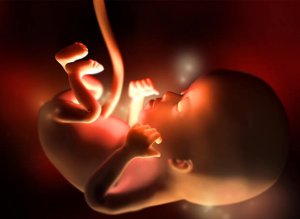

I den 12. svangerskapsuken, den siste i første trimester, kan babyens høyde være mellom 5 og 6 centimeter, og vekten mellom 8 og 14 gram. Hjertet slår veldig sterkt, med 160 slag per minutt, og bevegelsene begynner å øke, selv om de fremdeles forblir umerkelige for deg.

Babyens størrelse er omkring størrelsen til en plomme eller en pasjonsfrukt på dette svangerskapspunktet. Faktisk har fosteret vokst omtrent 15% mellom den forrige uken og den nåværende. Lemmene er allerede dannet, organene begynner å modnes raskt og til og med tarmen, som frem til til nå har vært koblet til basen av navlestrengen, beveger seg til bukhulen.

Hodet får på samme måte en avrundet form. Munnen kan åpnes og lukkes og ørene er der de hører hjemme. Neglene begynner å danne seg, det samme gjelder stemmebåndene. I løpet av den 12. svangerskapsuken begynner nyrene å produsere små mengder urin, og til og med de første tegnene på hår vises på kroppen.

Selv om kjønnet ennå ikke kan avgjøres med ultralyd, er kjønnsorganene i full utvikling på dette stadiet. På dette tidspunktet er babyen også i stand til å gjespe, hikke og svelge. Det er nå når naturens underverker virkelig begynner å bli synlige for oss, når vi ser de tingene vårt utviklende barn er i stand til å gjøre.